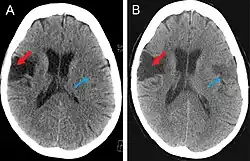

Scanning techniques include EEG, SPECT, MRI, and CT brain scanning.[1][2] These additional techniques are useful in determining what type of lesion the patient has, and allows physicians to determine more effective ways in treating the patient.

CT scan

This computer-tomography type of imaging is one of the most used in any clinical environment and although it can detect some of the brain areas affected by a stroke or a trauma it does not provide the same acuity as the magnetic resonance imaging. CT scans can also reveal, in patients with the syndrome, the bilateral cortical infarcts located in the posterior frontal region involving the opercular areas.[3]